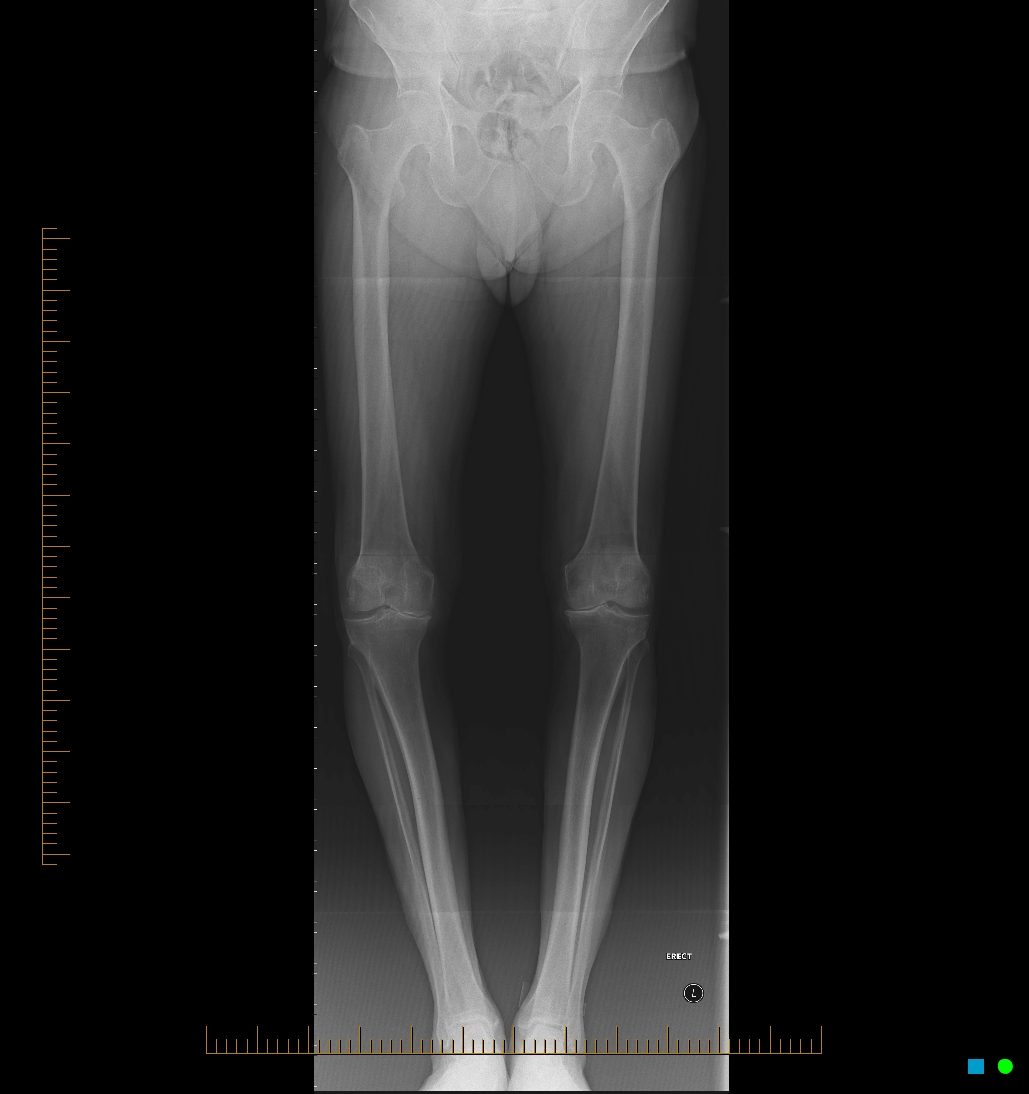

Este foarte importantă plănuirea tehnică a intervenţiei. De aceea pacientul este îndrumat către un serviciu de radiologie unde se vor efectua diverse tipuri de radiografii, printre ele fiind şi cele ale întregului membru inferior. Această radiografie este utilă deoarece prin intermediul ei se pot face diverse măsurători ce ajută chirurgul în timpul operaţiei să se adreseze diverselor defecte, astfel încât rezultatul să fie cel mai bun pentru pacient. Pentru diagnosticarea gonartrozei şi stabilirea indicaţiei de protezare a genunchiului nu este nevoie de alte investigaţii mai costisitoare cum ar fi rezonanţa magnetică (RMN). Radiografia este suficientă.